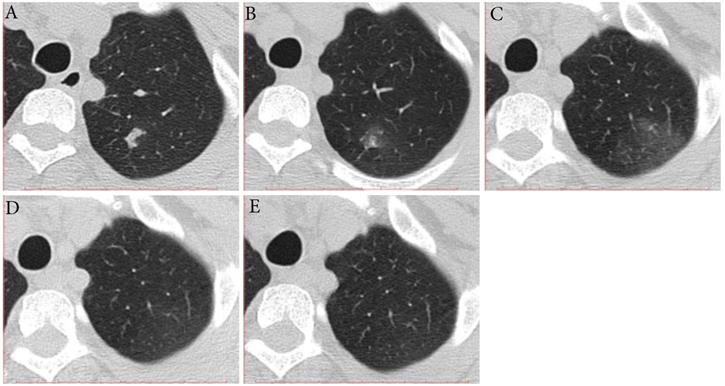

Three (16.7%) individuals showed type-MI, that is the trends of the extent and density were not similar to each other in the early stage and then improvement (Fig. 2). Two individuals showed the increase in long diameter and decrease in density on the second CT scans (2-3 days after the first positive SARS-CoV-2 result), followed by improvement. What's more, one individual showed the decrease in long diameter and increase in density on the second CT scan (7 days after the first positive SARS-CoV-2 result), followed by improvement. The interval time from first CT scans to last CT scans ranged from 14 to 24 days. The time for RT-PCR conversion of the three individuals ranged 14 to 26 days.

Figure 2

Typical evolution of type-MI in a 39-year-old female with asymptomatic SARS-CoV-2 infection. A, Day 0, the first chest CT showed a focal consolidation in apical posterior segment of left upper lobe. B-C, Day 2 and 6, the second to third CT scans showed increase in extent and decrease in density. D, Day 10, obvious resolution of the previous GGO was observed. E, Day 14, full resolution of the lesion was observed; and day 14 and 15, the patient had two consecutive negative results of RT-PCR. GGO, ground-glass opacity; MI, mismatch to improvement; RT-PCR, reverse transcriptase-polymerase chain reaction.